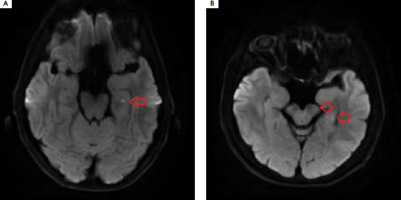

Figure I

Typical hyperintense foci in the diffusion-weighted magnetic resonance imaging of head located in the left hippocampus

Transient global amnesia (TGA) manifests as acute short-term memory disturbances with a distinctly marked component of anterograde amnesia, which spontaneously resolves within 24 hours, often leaving a gap in memory. Clinical symptoms typically last from 4 to 8 hours, rarely under 60 minutes (9-32%) [1]. The condition is more common in women and primarily occurs in the 6th to 7th decade of life. Diagnosis is based on the 1990 diagnostic criteria of Hodges and Warlow. During an episode, autopsychic orientation is preserved; however, due to impaired encoding of new memories, the patient is disoriented regarding time and place, leading them to ask the same questions repeatedly. No signs of focal damage to the central nervous system are observed. Magnetic resonance imaging (MRI) of the head performed 24 to 96 hours after the onset of symptoms shows minor hyperintense foci in the CA1 sector of one or both hippocampi in over 50% of patients, which are invisible in T2- weighted images and FLAIR sequences, disappearing after 7-10 days (Figure I). The prognosis is good. TGA is usually monophase, but recurrences occur in 2.9-26.3% of cases, with depression and migraines being predisposing factors [1].